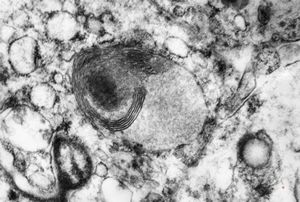

M,6m. | myelinoid inclusions in cerebral neuron - Nieman-Pick disease